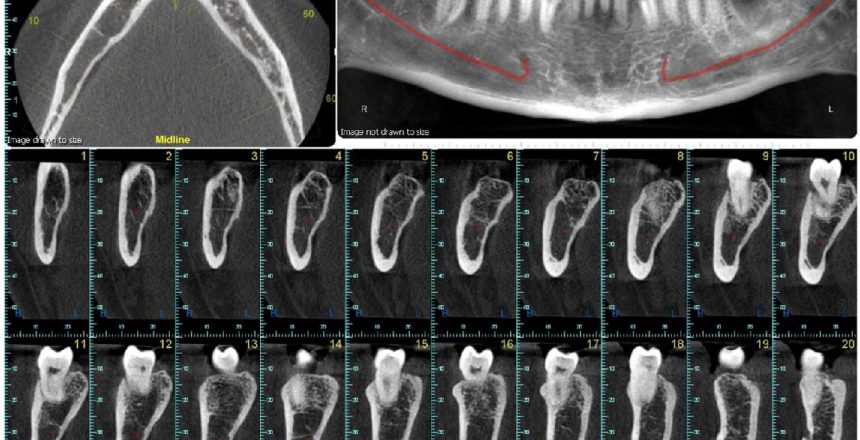

A tomografia é uma análise de partes do corpo similar aos raiosX. É realizada em um aparelho que usa os mesmos raios da radiografia, porém, oferece maior riqueza de detalhes na captura das imagens. A máquina utilizada para realização do exame realiza capturas transversais internas do corpo.

Depois que são registradas, as imagens serão tratadas num software de computador. O exame é utilizado para mostrar detalhes dos ossos, dentes e outras estruturas. Com essa imagem mais clara, o radiologista terá riqueza de informação, e passará diagnósticos mais precisos.

A diferença básica da radiografia e a tomografia, é que a primeira oferece apenas uma imagem da área que deve ser examinada, enquanto a segunda, pode gerar centenas imagens em múltiplos planos de visualização.